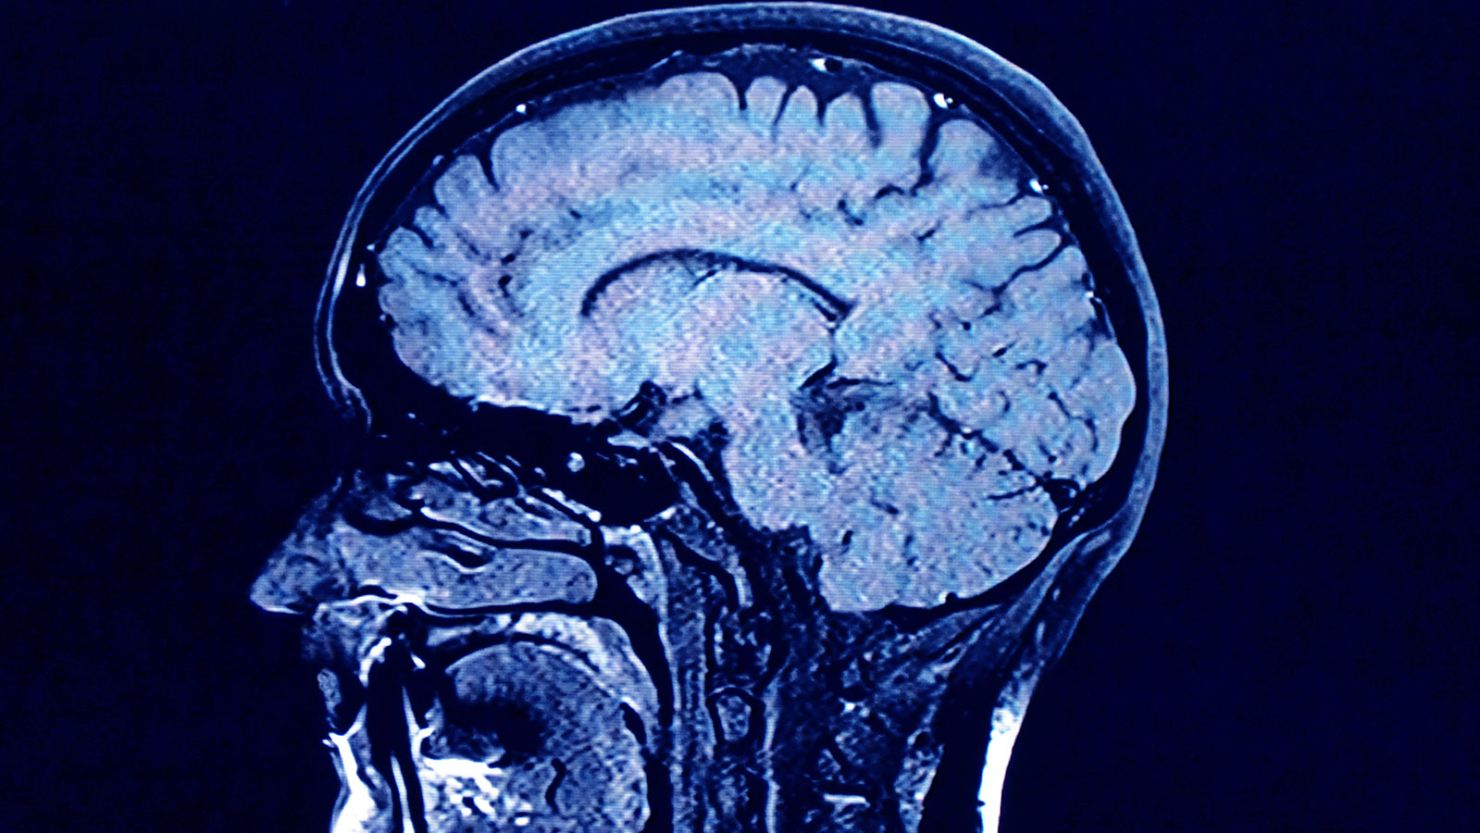

“We first took MRI scans of the participants when they were 73 years old. One of the most striking things about the study for me is how wide the differences are between their scans,” Cox wrote.

“Even though they were all the same age, some brains looked perfectly healthy (and wouldn’t be out of place amongst scans of 30 or 40 year olds),” he said. “Whereas others showed lots of shrinkage and damage to the white matter connections, along with other features that are related to cognitive ageing and dementia.”

White matter is the tissue that forms connections between brain cells and the rest of the nervous system, helping these regions communicate with each other through nerve signals. Having decreased or damaged white matter can slow the brain’s ability to process information.

Overall, “it shows us that brain ageing at age 73 is not an inevitability, while also strongly motivating us to research what we can do to emulate those lucky few who arrive at that age with such pristine brains,” Cox said.